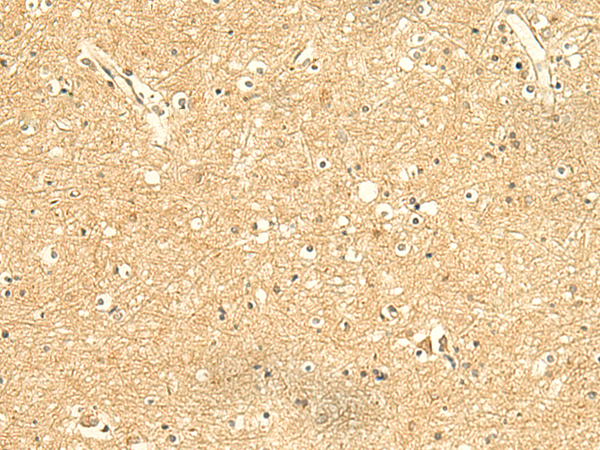

ELISA, IHC

IHC positive control:

Human tonsil and Human brain

IHC Recommend dilution:

50-300